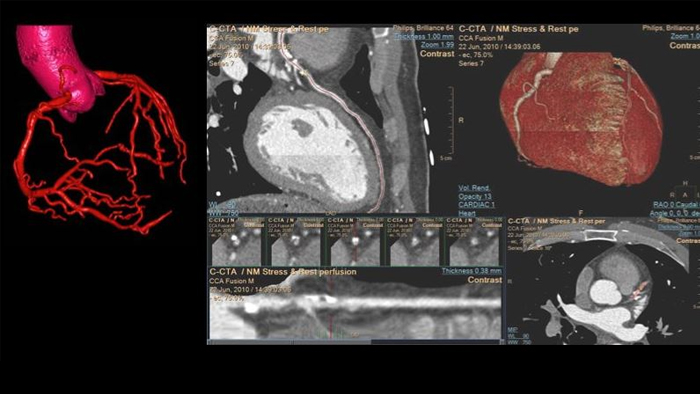

Philips Advanced Visualization Workspace

Review, analyze and quantify clinical information from different modalities and for various clinical indications with AI-enabled 3D models, maps and other quantitative tools.

Philips Cardiac CT

Unlock the full potential of CT as a non-invasive cardiac diagnostic tool.